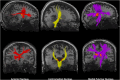

Figures